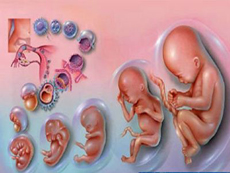

孕期的各項(xiàng)檢查,是準(zhǔn)媽媽們需要按時(shí)完成的重要任務(wù)。尤其是在懷孕的前三個(gè)月里,它是胎兒身體各器官發(fā)育的重要階段。其中胎心的發(fā)育成長(zhǎng)是最最關(guān)鍵的檢查項(xiàng)目,...